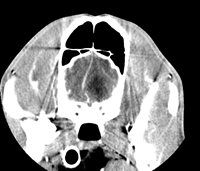

L'examen se déroule normalement en deux phases : une première phase d'acquisition d'images, dite sans préparation, suivie d'une deuxième phase, après injection d'un produit de contraste iodé par voie intraveineuse. Le produit de contraste permet de rehausser les structures vasculaires et certains tissus (en particulier les tumeurs). C'est la comparaison des deux séries d'images qui permet d'affiner le diagnostic tomodensitométrique.

Coupes Axiales : Thorax Caudal avant et après IV